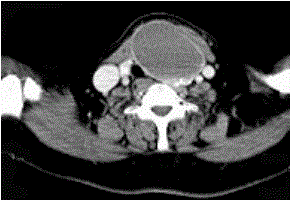

问题 女,56岁,发现颈部肿块30天,颈部肿大,无红肿热痛,无呼吸困难,无吞咽困难,无心悸胸闷烦躁史。近1个月来因肿大不适而来就诊。发病来饮食睡眠正常,体重无下降。如图所示该患者最可能诊断为()

选项 A.甲状舌管囊肿 B.甲状腺乳头状癌 C.甲状腺原发淋巴瘤 D.甲状腺腺瘤 E.甲状腺脓肿

答案 D